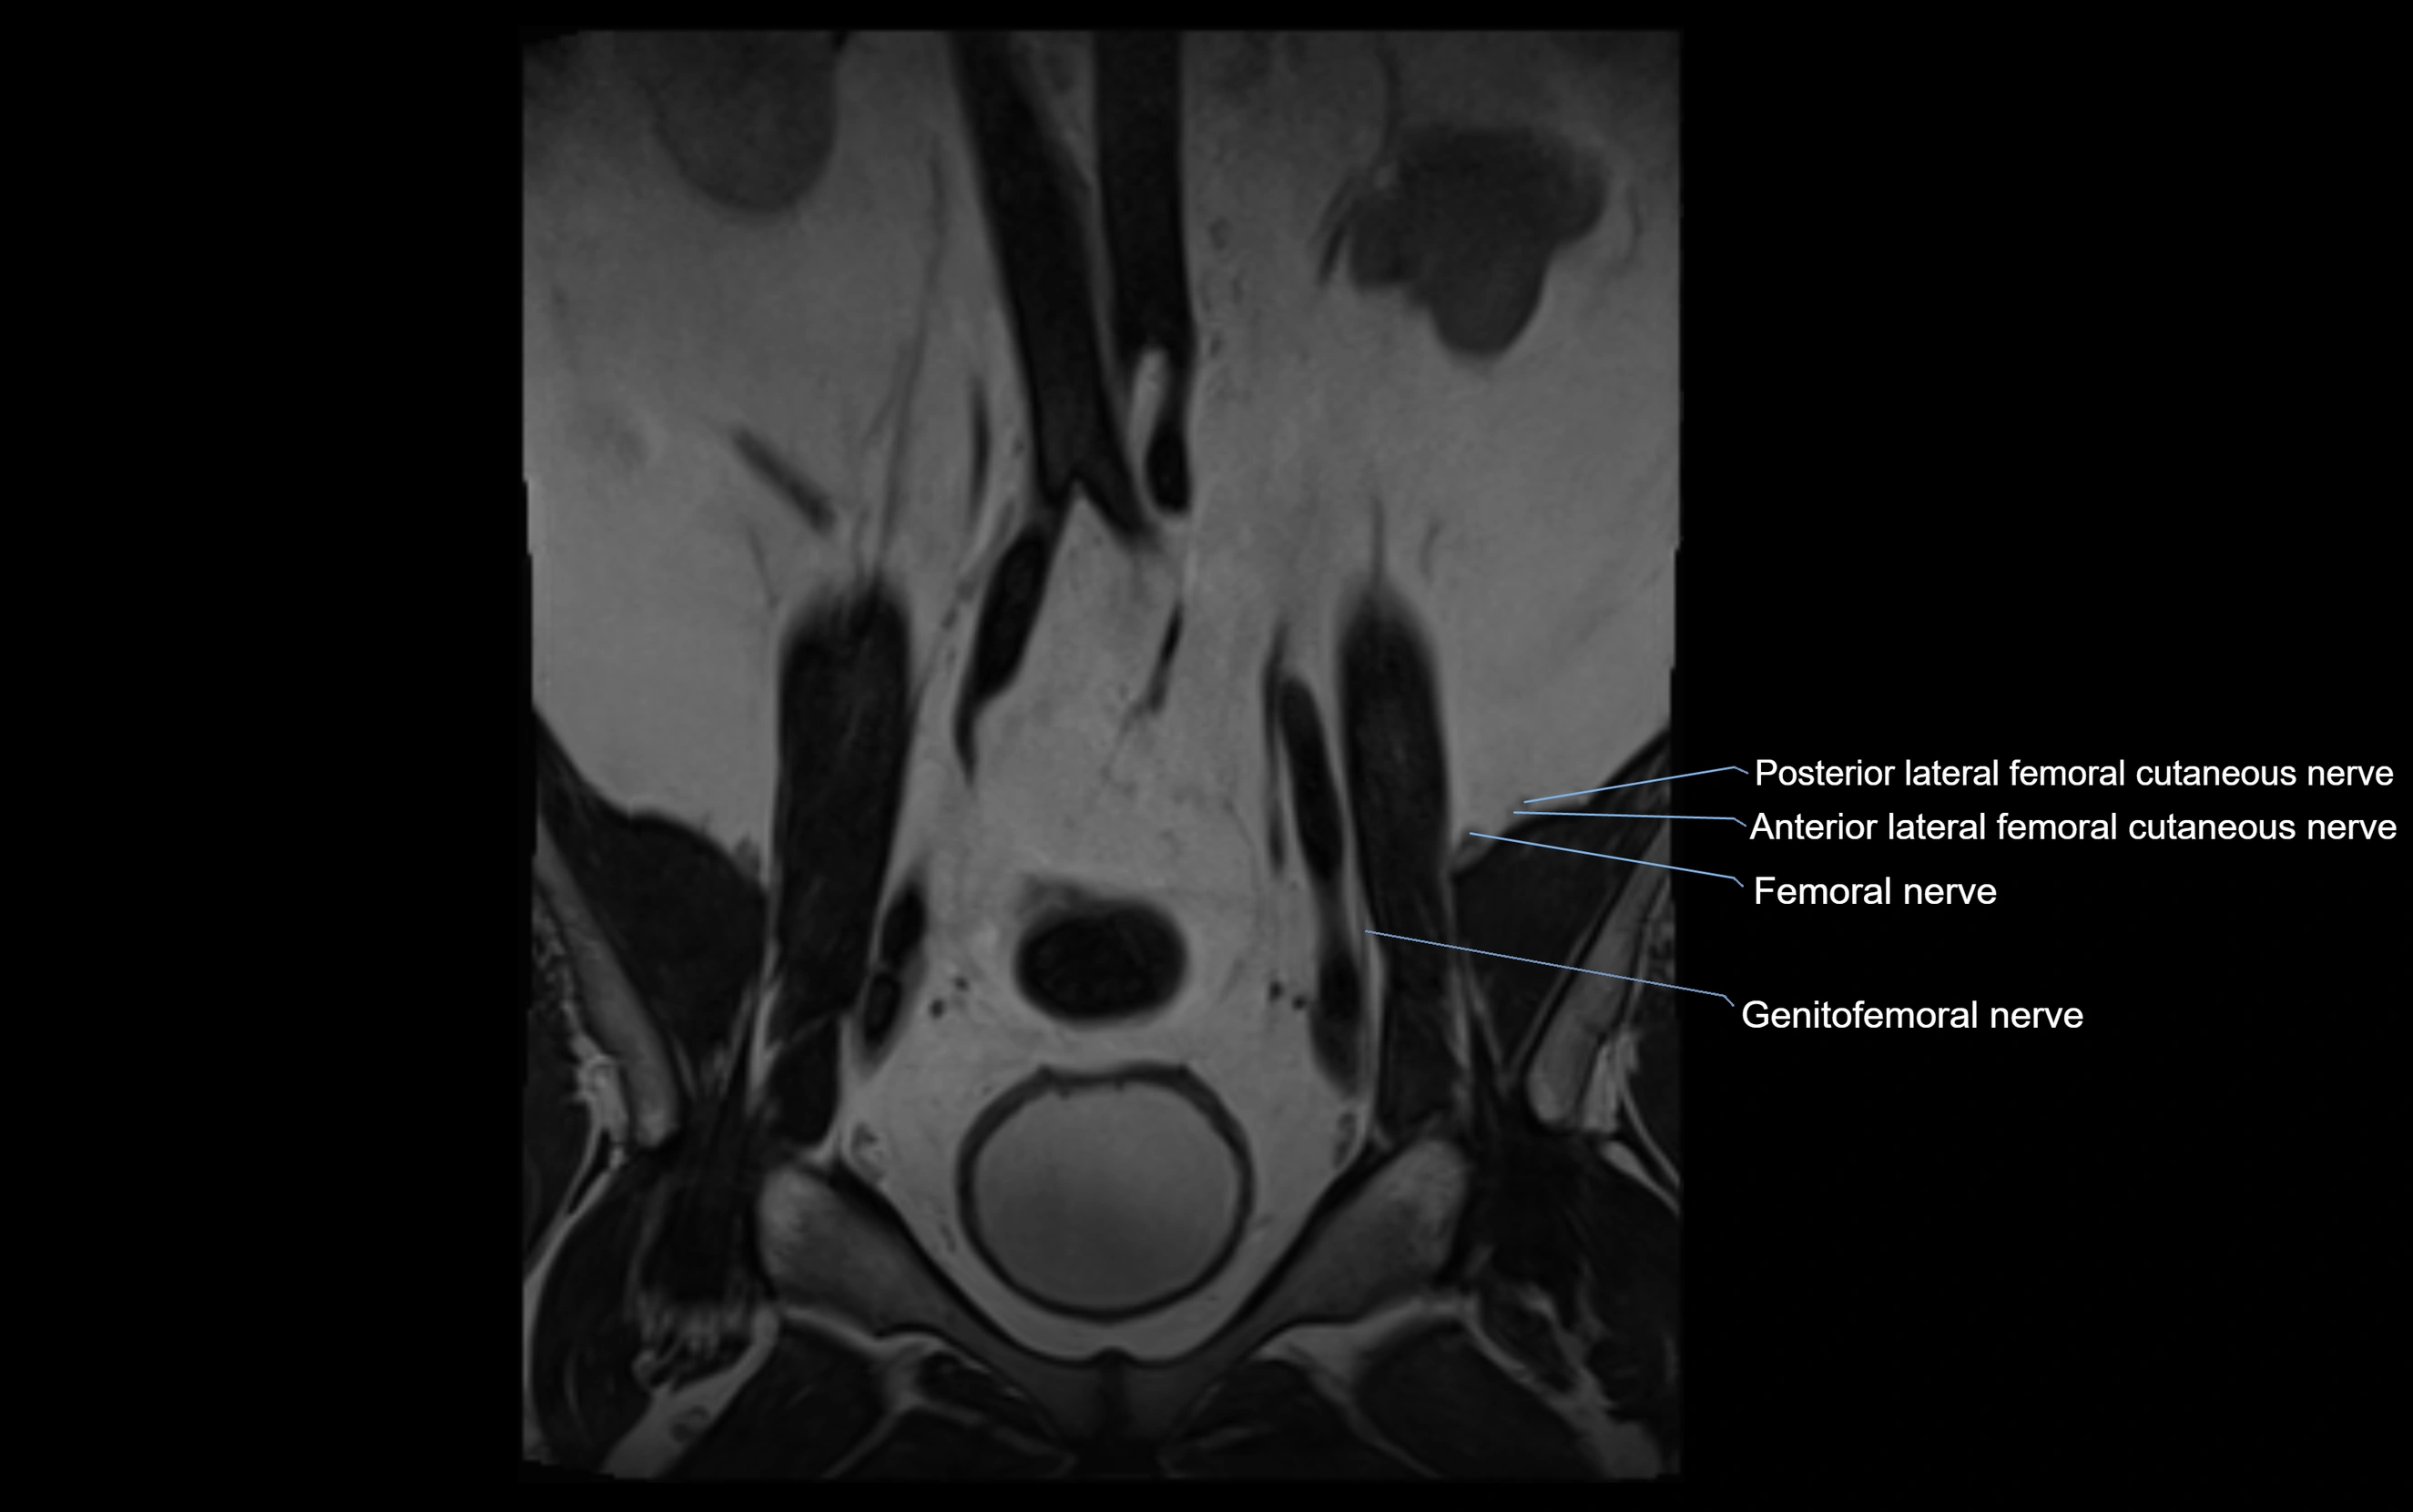

MRI Appearance

T1-weighted images:

• Nerve appears as a very thin low-to-intermediate signal intensity structure

• Surrounded by bright fat, aiding visualization

T2-weighted images:

• Nerve shows intermediate to mildly hyperintense signal compared to muscle

• Pathological involvement appears brighter

STIR (Short Tau Inversion Recovery):

• Normal nerve appears dark

• Inflamed or entrapped nerve appears bright hyperintense

T1 Fat-Sat Post-Contrast:

• Normal nerve enhances minimally

• Pathologic nerve (neuritis, entrapment, tumor infiltration) shows focal or diffuse enhancement

3D T2 SPACE / CISS:

• Nerve appears intermediate to mildly hyperintense compared to muscle

• Surrounded by bright fat or CSF, improving visualization

• Best sequence for mapping small pelvic nerves such as the anococcygeal